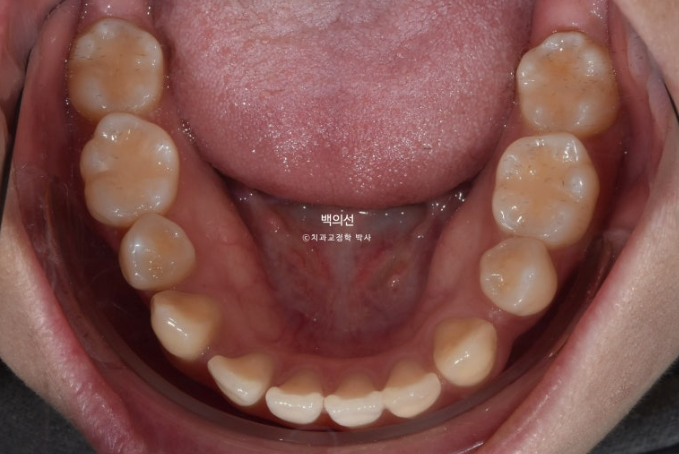

23.01

앞니 중심선이 다르고 아랫니에 듬성듬성 공간이 벌어져 있습니다.

아래에도 첫번째 작은어금니가 양쪽에 각각 결손되어 있네요. 그래서 공간들이 남아 치아들이 벌어져 있습니다.